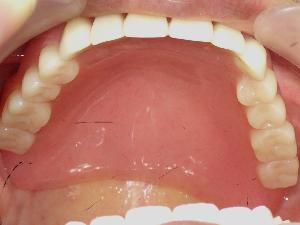

歯が1本もなくなってしまった場合に総入れ歯を使用します。 床の上に人工歯を並べた仕組みのものです。支える歯が無いため調整に比較的、時間がかかります。 |